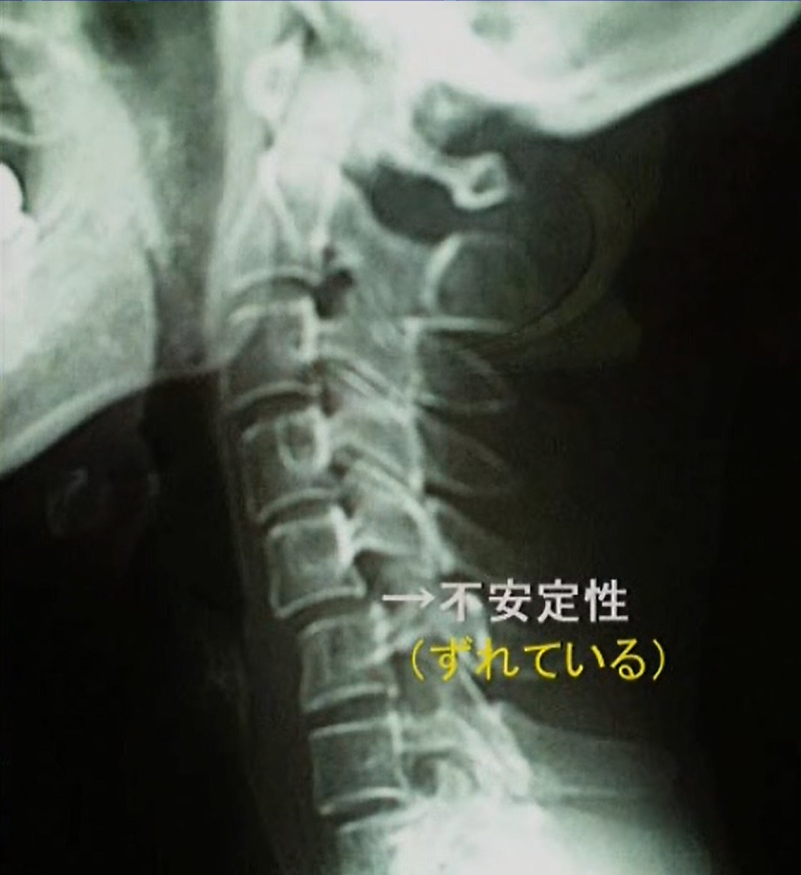

●不安定性

不安定性の確認をするために前後屈撮影をします。

下を向いて撮影、上を向いて撮影をするという事です。

本来、頸椎というのは前屈(下を向く)すると上位椎は下位椎の上で少し前に滑ります。

後屈(上を向く)と上位椎は下位椎の上で少し後ろに滑ります。

許容範囲は3mmまでと言われていますが、

右の写真を見ると正面を向いていますが前に滑っています。

これが不安定性の画像です。